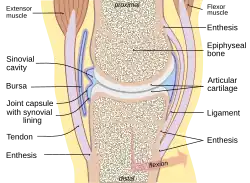

Das Kniegelenk (lateinisch Articulatio genus) ist das im Knie (lateinisch Genu, altgriechisch γόνυ gony) befindliche größte Gelenk der Säugetiere. Der Oberschenkelknochen (Femur), das Schienbein (Tibia) und die Kniescheibe (Patella) bilden dabei die knöchernen Gelenkkörper.

Das Kniegelenk ist ein zusammengesetztes Gelenk. Es besteht aus zwei Einzelgelenken, dem Kniescheibengelenk (Articulatio femoropatellaris), welches sich zwischen Oberschenkelknochen und Kniescheibe befindet, und dem Kniekehlgelenk (Articulatio femorotibialis), das zwischen Oberschenkelknochen und Schienbeinkopf (Caput tibiae) liegt. Anatomisch gesehen handelt es sich bei dem proximalen Gelenk zwischen Schienbein (Tibia) und Wadenbein (Fibula) (Articulatio tibiofibularis) zwar um ein eigenständiges Gelenk, das aber in der Regel über eine Ausbuchtung der Kniegelenkkapsel (Recessus subpopliteus) mit dem Kniegelenk verbunden ist.

Bänder

Da das Knie durch seine knöcherne Konstruktion sehr instabil ist, wird es durch zahlreiche Bänder gesichert. Sie verstärken damit die Gelenkkapsel, in deren äußere Schicht sie in der Regel eingebaut sind. Die Bänder des Knies werden nach ihrer Lage in vordere (ventrale), seitliche (kollaterale), hintere (dorsale) und zentrale Bänder eingeteilt.